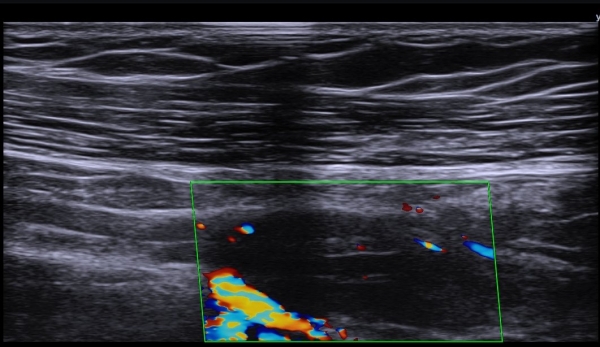

ÃÊÀ½ÆÄ  °Ë»ç  : À­ÆÈ ±ÙÀ§ºÎ Á¤Áß ½Å°æ Ⱦ´Ü¸é°Ë»ç¿¡¼­ Á¤Áß ½Å°æÀÇ ºÎÁ¾°ú ÀϺΠ½Å°æ¼¶À¯ÀÇ Àú¿¡ÄÚ ºÎÁ¾ÀÌ °üÂûµÈ´Ù

(»çÁø 1, 2). ŽÃËÀÚ¸¦ Á¶±Ù ´õ ±ÙÀ§ºÎ·Î À̵¿ÇÏ´Ï Á¤Á߽ŰæÀÇ Àú¿¡ÄÚ ºÎÁ¾ÀÌ °üÂûµÈ´Ù(»çÁø 3, 4).